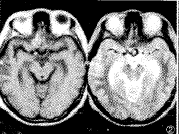

图1~5 患者,男 。蛛网膜下腔出血、右额血肿21天。

图2:MRI显示动脉瘤内血栓,额部出血。

MRI所见: 15例可在T1和T2WI上显示有异常的“流空信号簇”,其内流空信号有的不均 匀可见血栓形成(图2)。11例伴有蛛网膜下腔出血征象,9例伴有脑梗塞,11例未见异常。